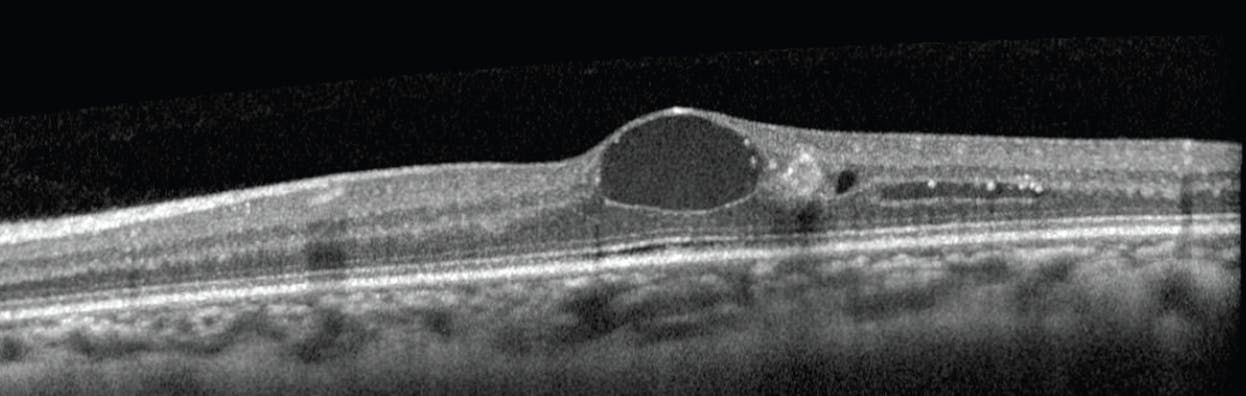

Most retina specialists have a low threshold to treat center-involving or center-threatening DME, especially for patients with perceived vision loss (Figure). The Early Treatment Diabetic Retinopathy Study (ETDRS) group was one of the first to document decreased vision related to the duration and severity of DME. In patients with a VA of 20/40 or better at baseline, the proportion of 3-line losers over 3 years increased from 5% of patients who did not develop severe DME to between 15% and 25% of those who developed severe DME for a duration of 4 to 12 months. In patients who developed severe DME for 28 to 36 months, 61% had moderately severe vision loss at 3 years.1

<p>Figure. When a patient presents with clear signs of DME on OCT imaging, clinicians have a low threshold to consider treatment with anti-VEGF agents, laser therapy, steroids, or PPV.</p>

Figure. When a patient presents with clear signs of DME on OCT imaging, clinicians have a low threshold to consider treatment with anti-VEGF agents, laser therapy, steroids, or PPV.